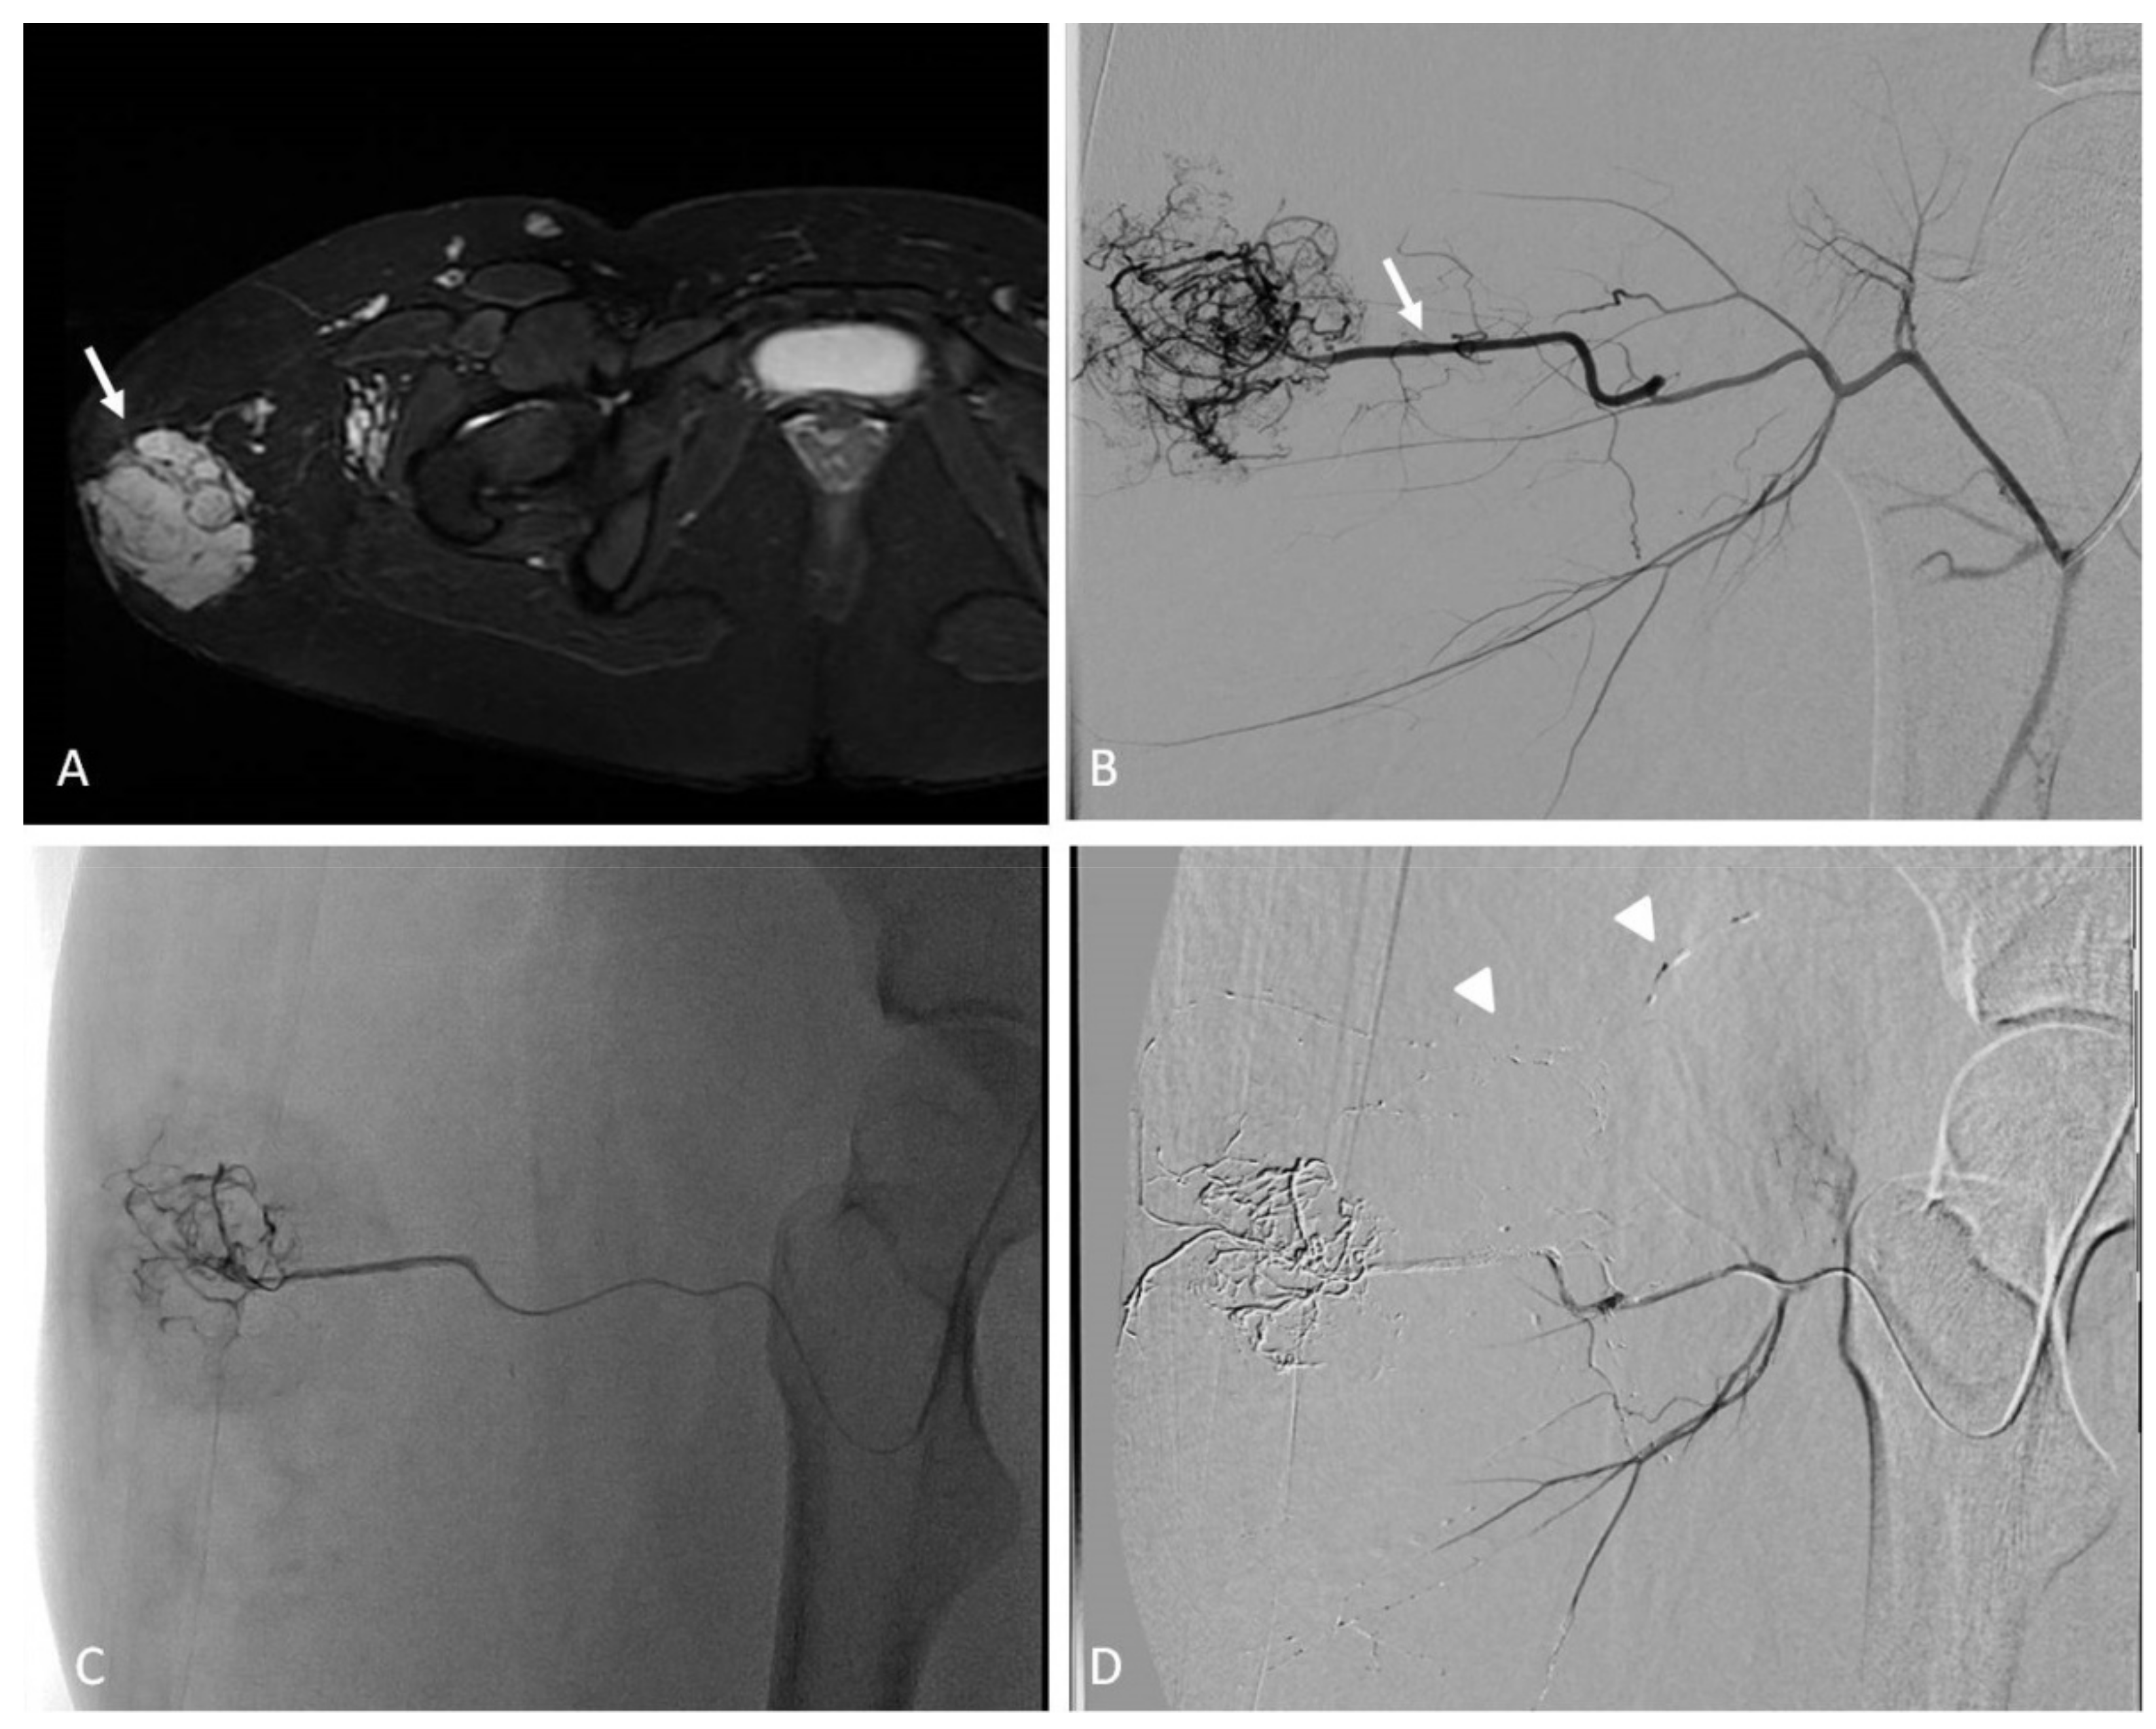

7. Congenital and Acquired Vascular Malformations (VMs)

7.1. Indications

7.2. Techniques

7.3. Clinical Outcomes